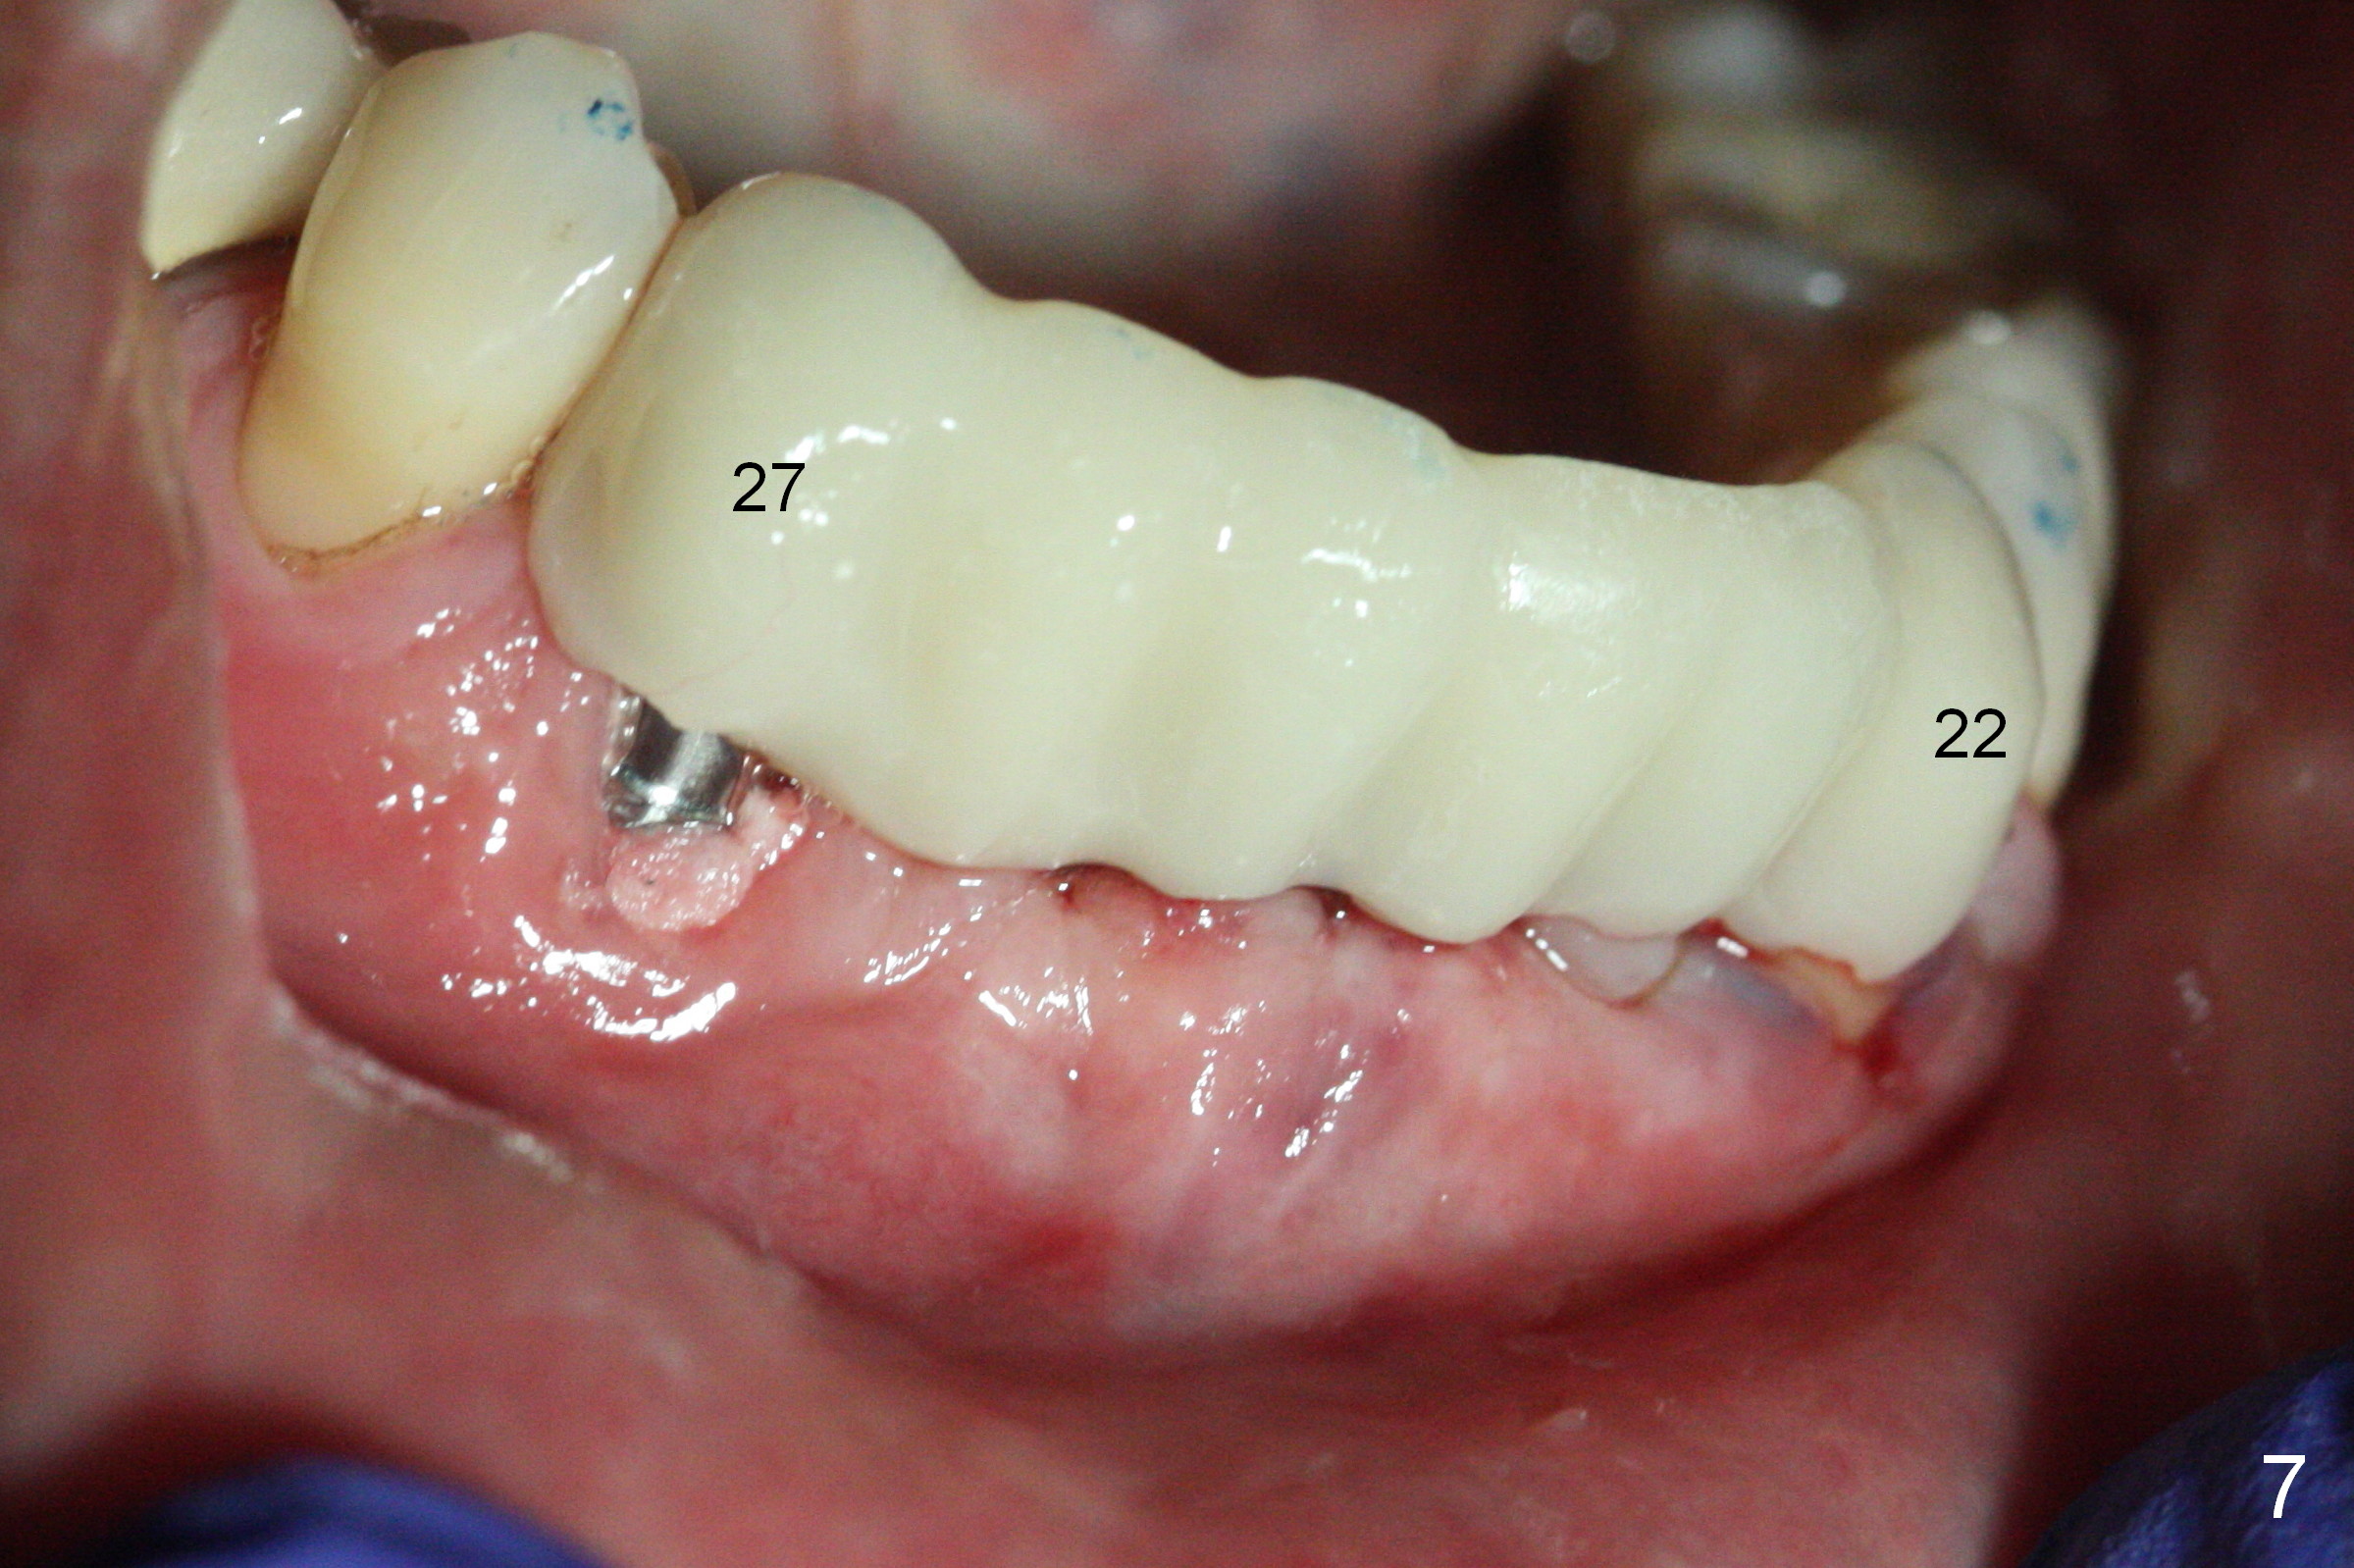

There is severe buccal gingival recession at #27 (Fig.1 arrow), as compared to that at #22. After removing the bridge and extraction of #27 (Fig.2 with severe loss of the buccal plate), a 3x18 mm drill is used to finish osteotomy (Fig.3). A 3.8x13 mm UF implant (Fig.3 green line) will be placed with 9 mm in the apparently solid, native (new) bone (blue line), while the coronal 5 mm will be occupied by the 5 mm cuff of a cemented abutment (pink line). The white dashed line is the gingival margin. The osteotomy is initiated as lingual as possible so that there will be at least 2 mm buccal gap when the narrow implant is placed. In spite of effort and precaution (guided surgery could control the trajetory), the coronal end of the implant tilts buccally so that a 4.5 mm 15 ° A 4 mm angled abutment is placed slightly subgingival (except buccal; Fig.5 A).

Since the ridge between the lower canines is atrophic (Fig.2), osteotomy starts at #23 and 25 after crestal reduction (Fig.4 arrowheads), Two of 2.5x12(4) mm 1-piece implants are placed (Fig.6). The implants at #23, 25 and 27 and the tooth #22 support an immediate provisional bridge (Fig.7).

The mesial defect at #27 appears to have been repaired 8 months postop (Fig.8,9 *); there is no bone loss at 1-piece implant sites. The gingival recession seems to remain the same before and after removal of the provisional FPD (Fig.10,11). The bulging abutment at the cervix is less prominent when a straight abutment is used and prepared (Fig.12, 4.5x5.5(5) mm). There is no bone loss at #23, 25 and 27 sites 2.5 years post cementation (Fig.12-15), although the trajectory of the implants could be improved by using surgical guide (Fig.16-18).